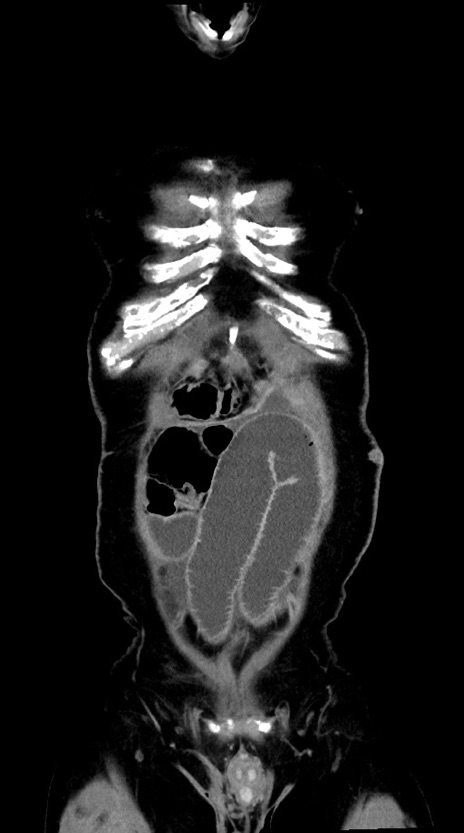

症例28(冠状断像)

【症例】60歳代男性

【主訴】嘔吐

【現病歴】胃癌にて胃全摘後。食思不振が悪化し、夜中に嘔吐することがある。

【既往歴】胃癌、胃全摘、脾摘、胆摘後

【データ】WBC 5900、CRP 10.56